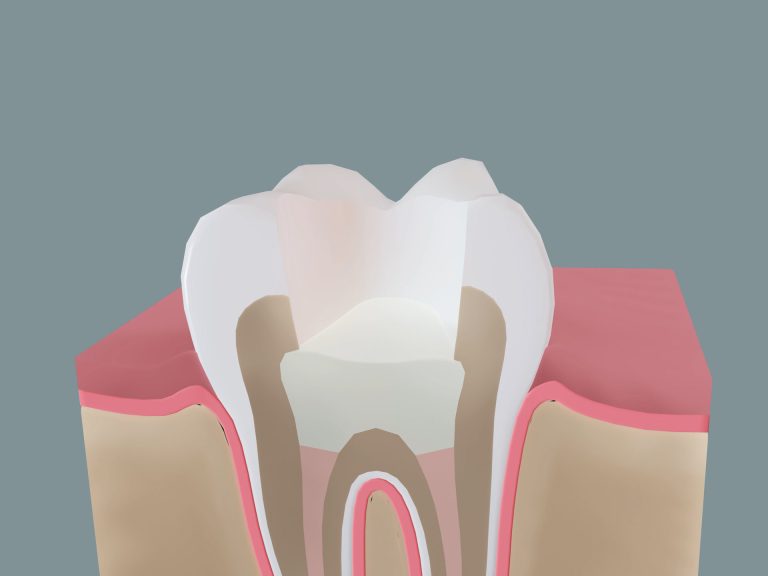

Let’s take a moment to picture what your tooth looks like from the inside.

Let’s take a moment to picture what your tooth looks like from the inside.

Each tooth is made up of several layers. The outermost layer, called enamel, is the hardest substance in your body and protects your tooth. Beneath that is dentin, a dense, supportive material that surrounds the inner chamber of the tooth, also known as the root canal. The dentin is the part of the tooth that responds to stimuli, such as temperature.

Inside this space lives the pulp, a soft tissue containing nerves, blood vessels, and connective tissue. This is what gives your tooth feeling and also what can become infected if decay, cracks, or damage reach too deep.